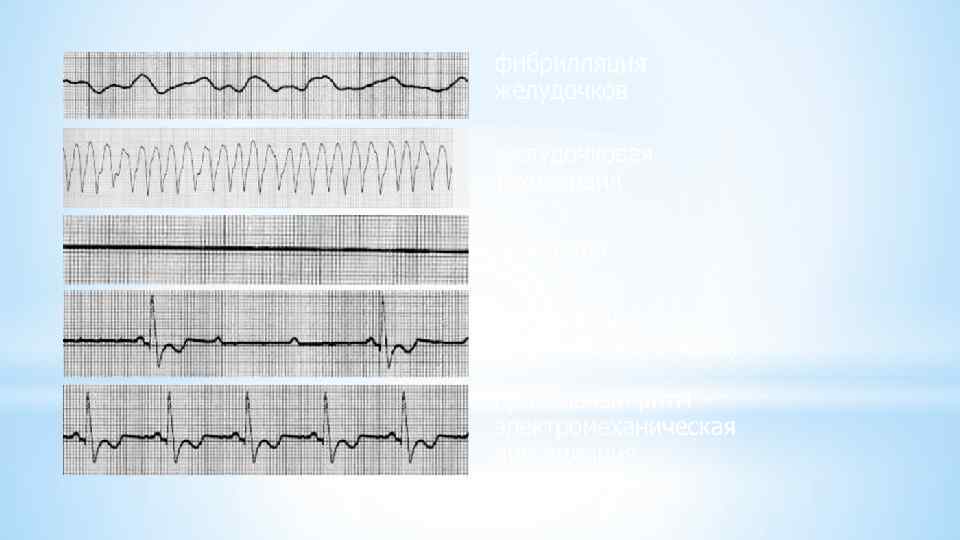

* Поскольку при возникновении фибрилляции желудочков насосная функция сердца прекращается, отмечается картина внезапной остановки кровообращения и клинической смерти. Больные теряют сознание, что часто сопровождается судорогами, непроизвольными мочеиспусканием и дефекацией. Зрачки расширены и не реагируют на свет. * Развивается диффузный цианоз, отсутствуют пульсация на крупных артериях — сонных и бедренных — и дыхание. Если в течение 4 мин не удается восстановить эффективный сердечный ритм, наступают необратимые изменения в центральной нервной системе и других органах. * При трепетании желудочков МОС, сознание и АД, обычно низкое, на короткое время могут сохраняться. В большинстве случаев, однако, этот неустойчивый ритм довольно быстро переходит в фибрилляцию желудочков. * На ЭКГ фибрилляция желудочков проявляется различными по амплитуде и продолжительности хаотическими волнами мерцания с недифференцирующимися зубцами и частотой более 300 в 1 мин. В зависимости от амплитуды этих волн различают крупно - и мелковолновую фибрилляцию. При крупноволновой фибрилляции амплитуда волн превышает 5 мм, при мелковолновой фибрилляции - не достигает этой величины.

* Поскольку при возникновении фибрилляции желудочков насосная функция сердца прекращается, отмечается картина внезапной остановки кровообращения и клинической смерти. Больные теряют сознание, что часто сопровождается судорогами, непроизвольными мочеиспусканием и дефекацией. Зрачки расширены и не реагируют на свет. * Развивается диффузный цианоз, отсутствуют пульсация на крупных артериях — сонных и бедренных — и дыхание. Если в течение 4 мин не удается восстановить эффективный сердечный ритм, наступают необратимые изменения в центральной нервной системе и других органах. * При трепетании желудочков МОС, сознание и АД, обычно низкое, на короткое время могут сохраняться. В большинстве случаев, однако, этот неустойчивый ритм довольно быстро переходит в фибрилляцию желудочков. * На ЭКГ фибрилляция желудочков проявляется различными по амплитуде и продолжительности хаотическими волнами мерцания с недифференцирующимися зубцами и частотой более 300 в 1 мин. В зависимости от амплитуды этих волн различают крупно - и мелковолновую фибрилляцию. При крупноволновой фибрилляции амплитуда волн превышает 5 мм, при мелковолновой фибрилляции - не достигает этой величины.

Крупно- и средневолновая фибрилляция желудочков.

Крупно- и средневолновая фибрилляция желудочков.

*Основные ЭКГ признаки фибрилляции желудочков • Отсутствие на ЭКГ типичной кривой с дифференцированными привычными зубцами P, Q, R, S и T. * • Вместо них регистрируются небольшие различные по величине (0, 1 -0, 3 m. V), неодинаковой формы волны фибрилляции. * • Расстояние между пиками волн различны. *Нет четкой изолинии; кривая фибрилляции приобретает хаотическую причудливую форму.

*Основные ЭКГ признаки фибрилляции желудочков • Отсутствие на ЭКГ типичной кривой с дифференцированными привычными зубцами P, Q, R, S и T. * • Вместо них регистрируются небольшие различные по величине (0, 1 -0, 3 m. V), неодинаковой формы волны фибрилляции. * • Расстояние между пиками волн различны. *Нет четкой изолинии; кривая фибрилляции приобретает хаотическую причудливую форму.